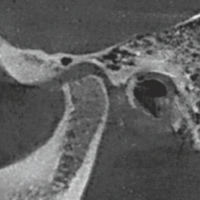

Figure 1: Anteroposterior and lateral view of X-ray showing Type 6 tibial plateau fracture with metaphyseal diaphyseal disassociation.

Figure 2: Image showing staple 5 locking screw fixation for proximal fragments. Immediate Postoperative X-ray.